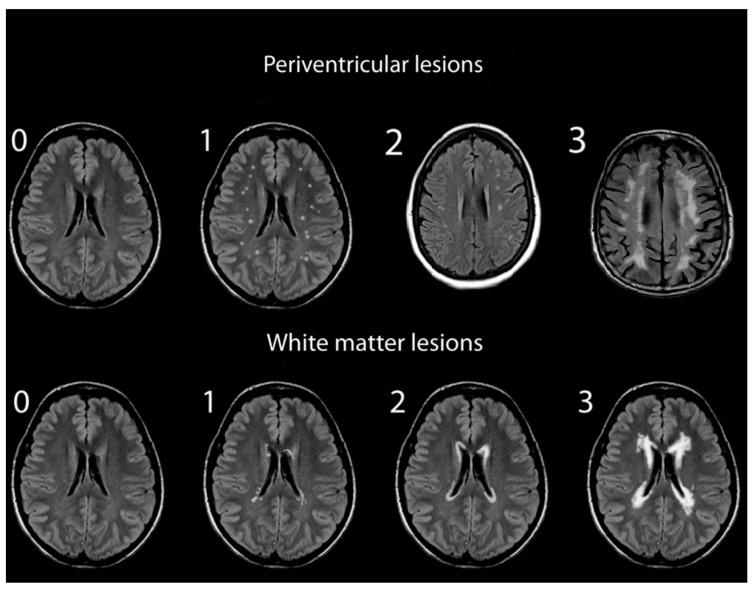

T2-weighted MRI scans of 150 patients with SSNHL were assessed for WMHs and compared with the data of 148 healthy age-matched adults. Assessments of WMHs included independent grading of deep white matter hyperintensities (DWMHs) and periventricular hyperintensities (PVHs). WMH severity was visually rated using the Fazekas and Mirsen scales by two independent observers.

方法

对150例SSNHL患者进行T2加权MRI扫描以评估WMHs,并与148例年龄匹配的健康成年人的数据进行比较。WMHs的评估包括对深部白质高信号(DWMHs)和脑室周围高信号(PVHs)进行独立分级。由两名独立观察者使用Fazekas和Mirsen量表对WMH严重程度进行视觉评分。